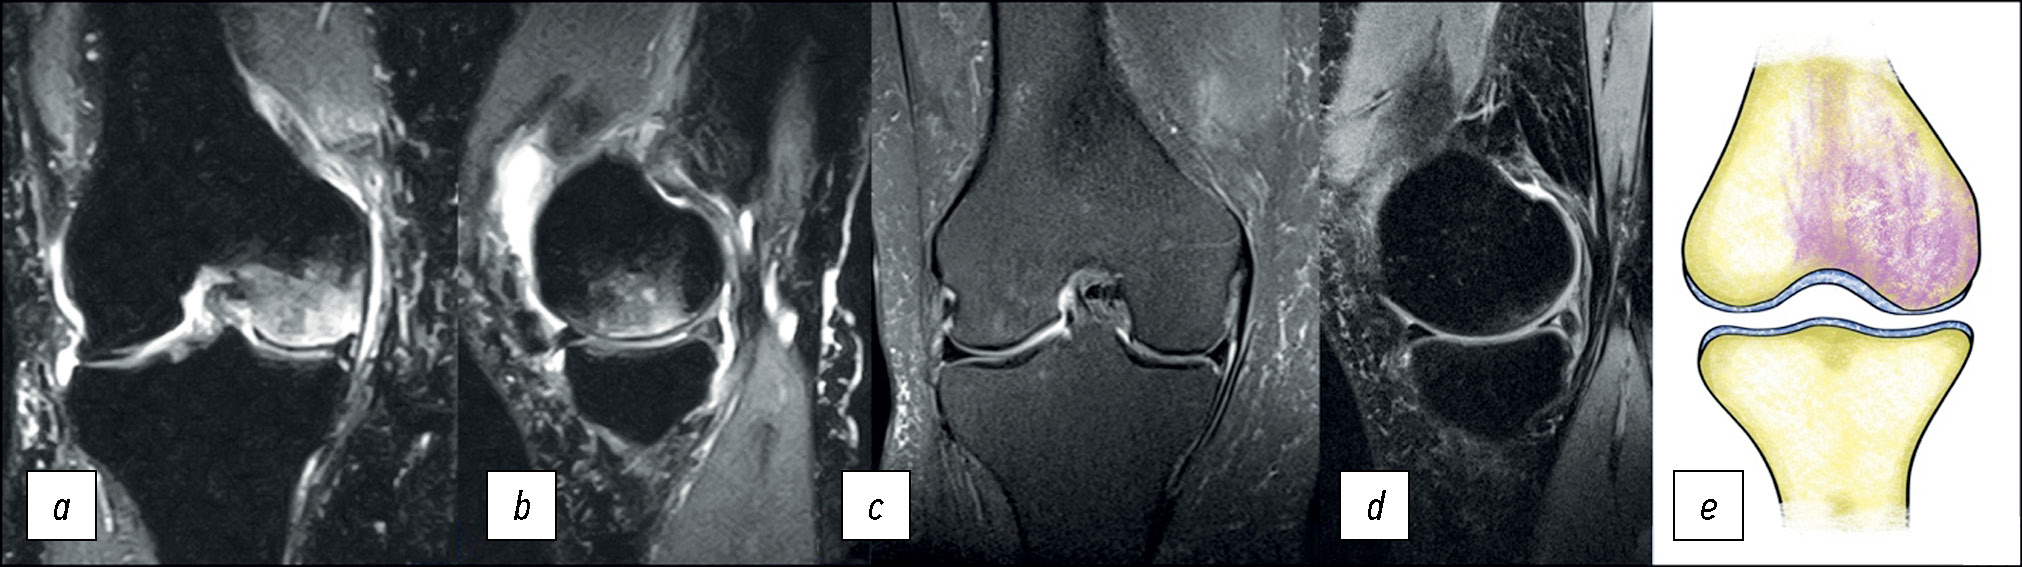

Пациентка Б., 44 года, обратилась с жалобами на боль в правом коленном суставе. Боль беспокоит в течение 6 месяцев. Из анамнеза известно, что в течение 15 лет пациентка больна системной красной волчанкой и постоянно получает глюкокортикоиды. После выполнения МРТ (рис. 6) поставлен диагноз: вторичный лекарственный остеонекроз костей (M87.1).

Рис. 6. МР-томограммы коленного сустава: a, b — корональная и сагиттальная проекции в режиме PD с подавлением сигнала от жировой ткани при вторичном лекарственном остеонекрозе, с — корональная проекция в режиме Т1; d — графическое изображение.

Fig. 6. MRI scans of the knee: a, b — coronal and sagittal views in to suppress the signal from adipose tissue with a secondary osteonecrosis of the knee (SOK), с — coronal views in T1-weighted sequences, d — graphic image.

Особенностью отёка костного мозга при вторичном остеонекрозе на фоне приёма глюкокортикоидов, лучевой или химиотерапии является наличие характерного географического рисунка, который развивается в результате нарушения кровоснабжения, приводящего к гибели клеток трабекулярной кости. Подобная змеевидная полоса с двойным контуром идентифицируется у 65–85% пациентов [13].

Внутренняя гиперинтенсивная полоса (T2-режим) обусловлена репаративной грануляционной тканью, а внешняя гипоинтенсивная полоса — склерозом, отделяющим зону поражения от здоровой кости и являющимся патогномоничным признаком вторичного остеонекроза [14].